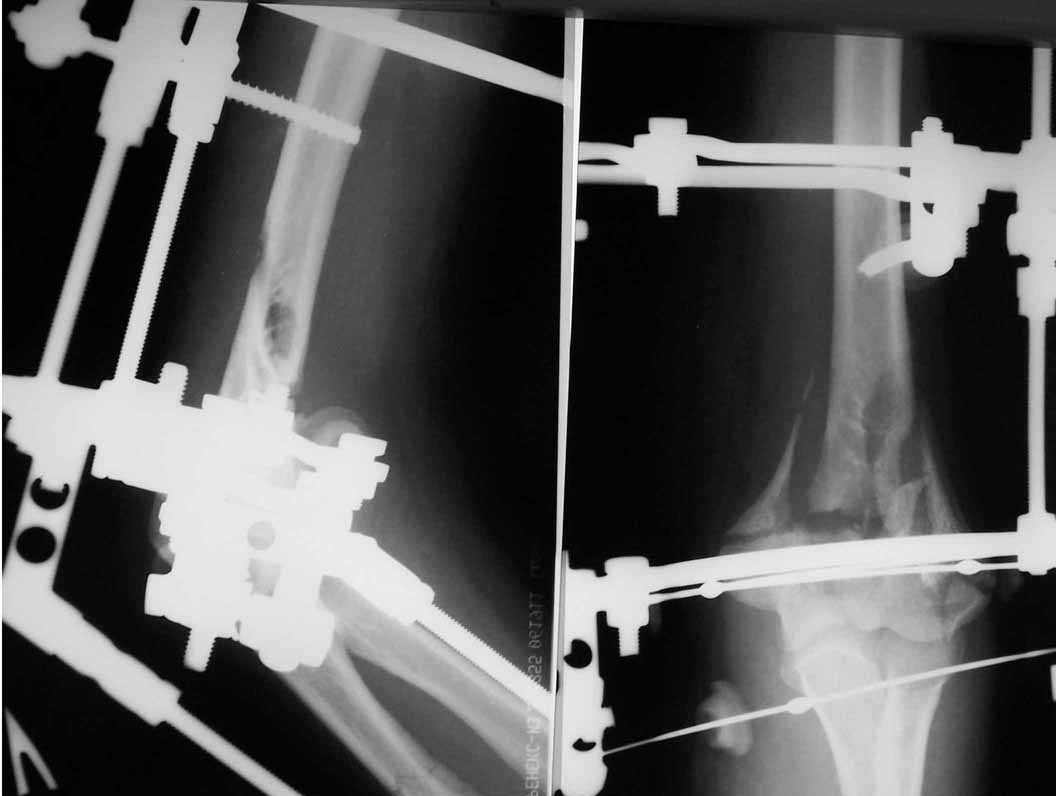

Женщина 42 лет, операция через неделю после перелома.

Д-з - открытый перелом мыщелков со смещзением и локтевой кости

без смещения - падение с лошади.

Остеосинтез закрытый (если так можно выразиться), т.е. без

разрезов. Длительность операции - около 1,5 часа со студентом.

6 щелчков ЭОПом.